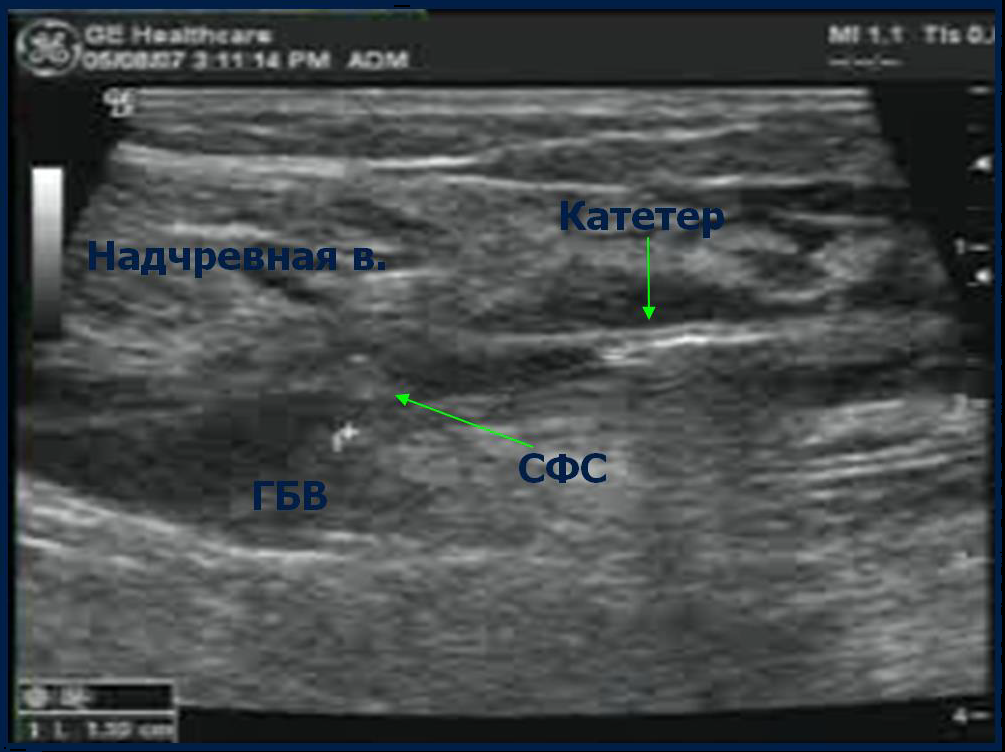

Предоперационная разметка на УЗИ

• Сафено-феморальное соустье

• Глубину залегания вены (< 10 мм от поверхности кожи)

• Минимальный и максимальный диаметры вены

• Особенности анатомии - Извилистые и расширенные сементы, Удвоение вены, Притоки, Ветви и перфоранты

• Места возможного доступа

ФИНАЛЬНЫЙ КОНТРОЛЬ ПОЛОЖЕНИЯ КОНЧИКА КАТЕТЕРА

Под контролем УЗИ убедитесь, что кончик катетера расположен на 2 см дистальнее СФС